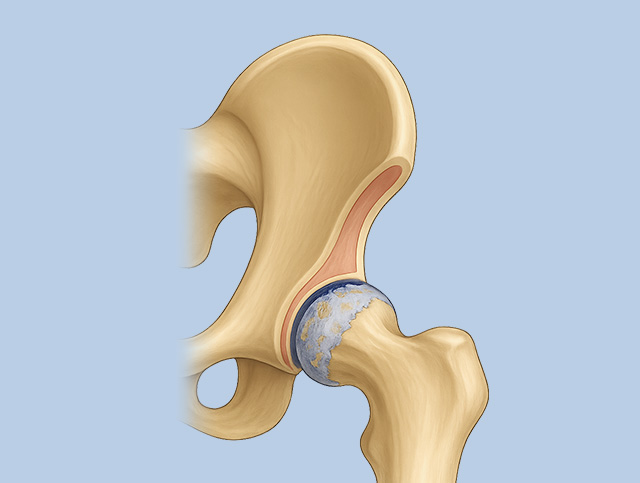

고관절 충돌증후군

허벅지뼈의 둥근 머리와 골반의 움푹 들어간 고관절 연결 부위가 부딪히면서 염증, 통증 발생

골반 앞쪽이나 사타구니 쪽 통증, 다리를 돌리거나 양반다리 하기 어려워짐. 악화되면 허벅지, 엉덩이, 허리까지 통증 확산

퇴행성 고관절염

고관절에 염증이 발생하여 통증, 절뚝거림, 고관절 움직임 제약

고관절 연골 두께 감소, 활액막 두꺼워짐, 물이 차는 증상 등 발생

고관절의 연골, 힘줄, 뼈 등 세부 조직의

염증, 손상의 정도와 유발 요인에 대한

의학 · 한의학의 통합적 진단 하에 맞춤치료